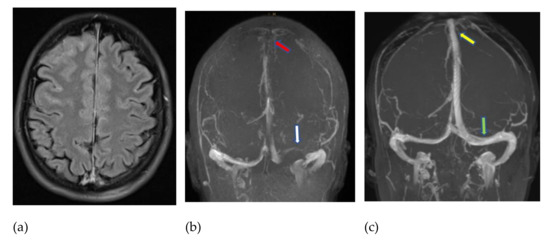

3.1. Patient #1

3.2. Patient #2

3.3. Patient #3